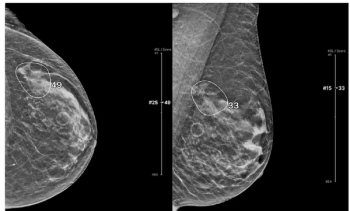

An emerging deep learning algorithm had a lower AUC and sensitivity than urological radiologists for differentiating between small renal masses on computed tomography (CT) scans but had a 21 percent higher sensitivity rate than non-urological radiologists, according to new research.